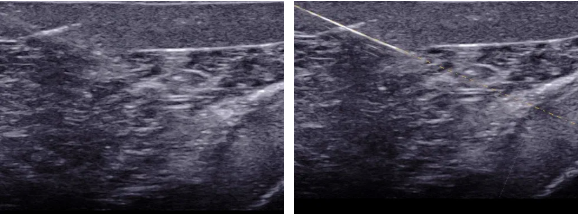

介入超声是在超声引导下将穿刺针、导管等医疗器具准确的进入靶目标从而达到诊断和治疗的一种手术手段,介入超声包括细针穿刺活检(FNA)、置管引流、囊肿硬化、结节的热消融。超声引导下穿刺介入手术就是在超声仪器检测下可直接观察到病灶目标,定位后将穿刺针对准靶目标后进行抽吸,如抽取肿瘤的实质是行组织或细胞的活检,胸水、腹水抽吸是实行抽液治疗。穿刺方法分为平面内穿刺和平面外穿刺,平面内穿刺是指沿探头长轴方向的穿刺A图所示,平面外穿刺是指探头短轴上的穿刺B图所示。

甲状腺FNA过程图

A平面内穿刺                                  B平面外穿刺